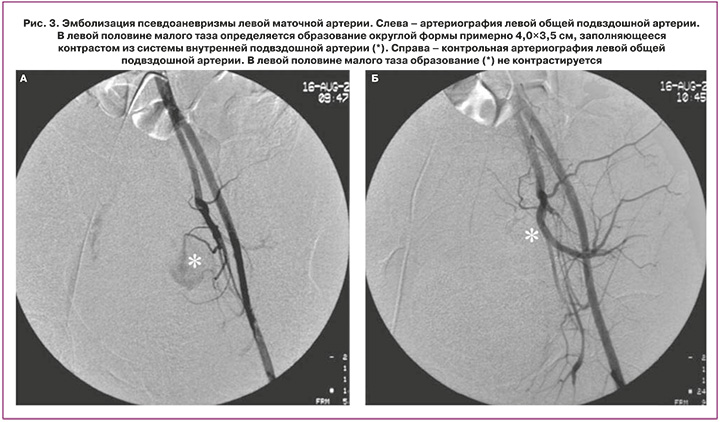

При селективном контрастировании из левой внутренней подвздошной артерии определяются две питающие образование (*) артерии (стрелки) (рис. 1). Суперселективно катетер проведен в нижнюю питающую артерию, имплантирована спираль IMWCE-35-3-5 («Cook Medical»). Затем катетер установлен суперселективно в верхней питающей артерии, при артериографии заполняется только псевдоаневризма (рис. 2а). В полость аневризмы введено 100 мг частиц поливинилалкоголя размером 500 мк («Cook Medical»), однако снижения кровотока и тромбирования аневризмы не последовало. Имплантирована спираль IMWCE-35-3-5 («Cook Medical»). При артериографии питающей артерии через 3 минуты псевдоаневризма не заполняется (рис. 2б). При артериографии левой общей подвздошной артерии с ручным контрастированием объемное образование (*) в проекции матки слева не контрастируется (рис. 3). Также выполнена артериография правой общей подвздошной артерии с ручным контрастированием – данных за контрастирование аневризмы из ветвей внутренней подвздошной артерии не получено. Катетер и интродьюсер извлечены, гемостаз области катетеризации 10 мин. Давящая повязка.